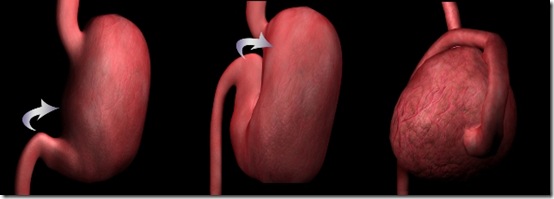

Es ist ein ziemlich häufiger auftreten in ’ ’ Dogge und der großen Mole. UND’ wahrscheinlich aufgrund der Beziehung zwischen den Brustkorb und Tiefe. UND’ einfacher, als es zu verhindern. Verdrehung ist mehr oder weniger vollständig den Magen um seine Längsachse, die der Cardia und Pflock endet. Die betreffenden Krankheit ist immer noch Gegenstand von Forschung und Studium in wenn nicht vollständig bekannt.Zeigen Sie prädisponierende Elemente reichliche Mahlzeiten und verschluckt schnell, gewalttätige und übertriebene Bewegungen, Sprünge, fällt, abrupten Verschiebungen, einen vollen Magen gemacht. Es scheint, dass es auch eine hereditäre Komponente, die eine Situation wo ösophageale fördern könnte Mobilität prädisponierenden Anatomie, Entspannung des Zwerchfells und Bauch Strukturen und Systeme der Fixierung des Magens. Es bleibt die Tatsache, dass der Magen um seine Längsachse und manchmal übertraf die kommenden 180 ° gedreht. Dies bewirkt, dass die Schließung der Magen Öffnungen (Kardia und Stange) resultierende Gärung Gas- und dann schnell und beeindruckende Zunahme des Volumens des Magens: Es folgt Membran-Komprimierung, ernsthafte Veränderungen der Magen Schiffe, Splenomegalie, etc..

Drehung, die den Magen während einer Torsion macht

Die Drehung im Uhrzeigersinn beginnt mit einer Wasserverdrängung von Pylorus und ’ Höhle die führen von rechts Bauchwand an der Mittellinie und dann bewegen Sie über dem Boden und den Körper des Magens und werden im linken Quadranten des Bauches während der Körper ’ Magen befindet sich im rechten Quadranten.

Quelle des Bilds ’ www.mondomalamute.EU